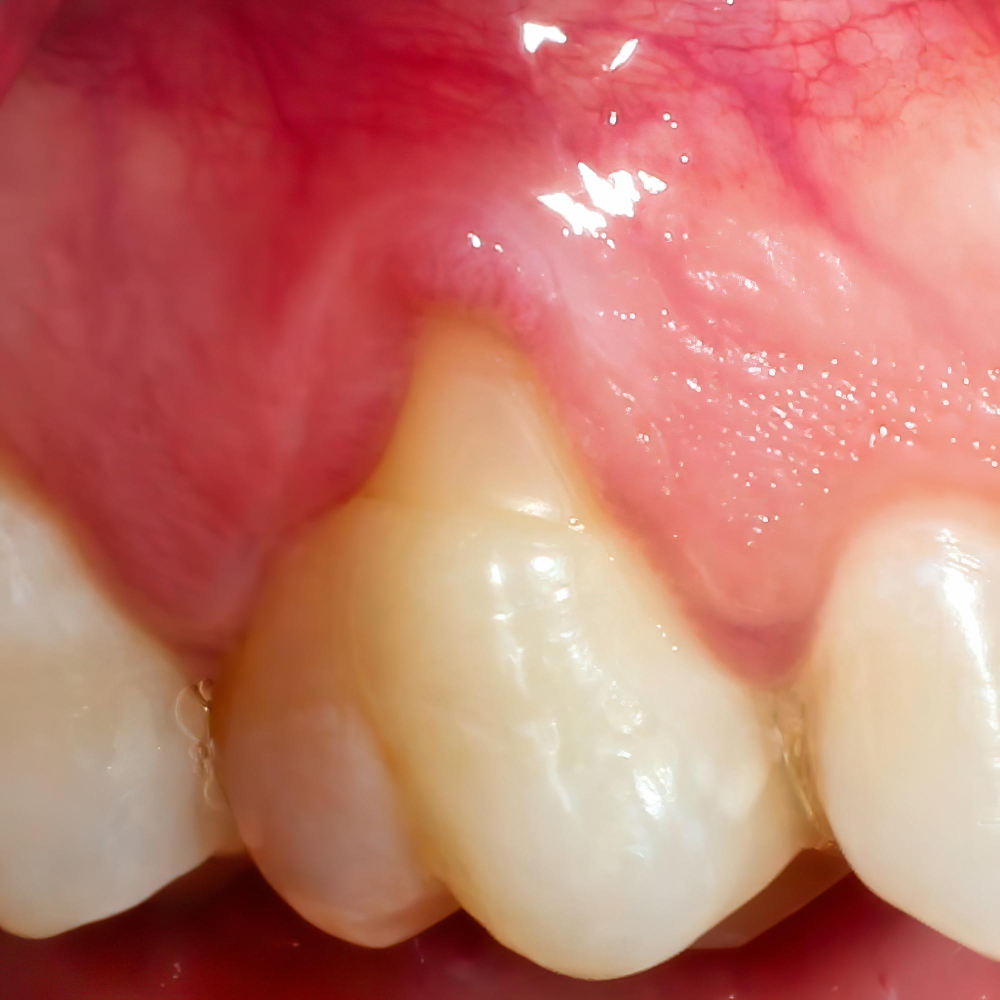

La periodontitis es una enfermedad inflamatoria de origen bacteriano que destruye el hueso y el ligamento que sostienen los dientes. Es la fase avanzada de una gingivitis no tratada, y se caracteriza por la formación de bolsas periodontales, encías retraídas y movilidad dental.

A medida que avanza, el hueso de soporte se pierde de forma irreversible. Pero si se detecta a tiempo y se trata adecuadamente, es posible frenar la progresión y conservar los dientes.

- Encías retraídas (dientes que parecen más largos)

- Sangrado espontáneo o al cepillarse

- Pus o inflamación en la encía